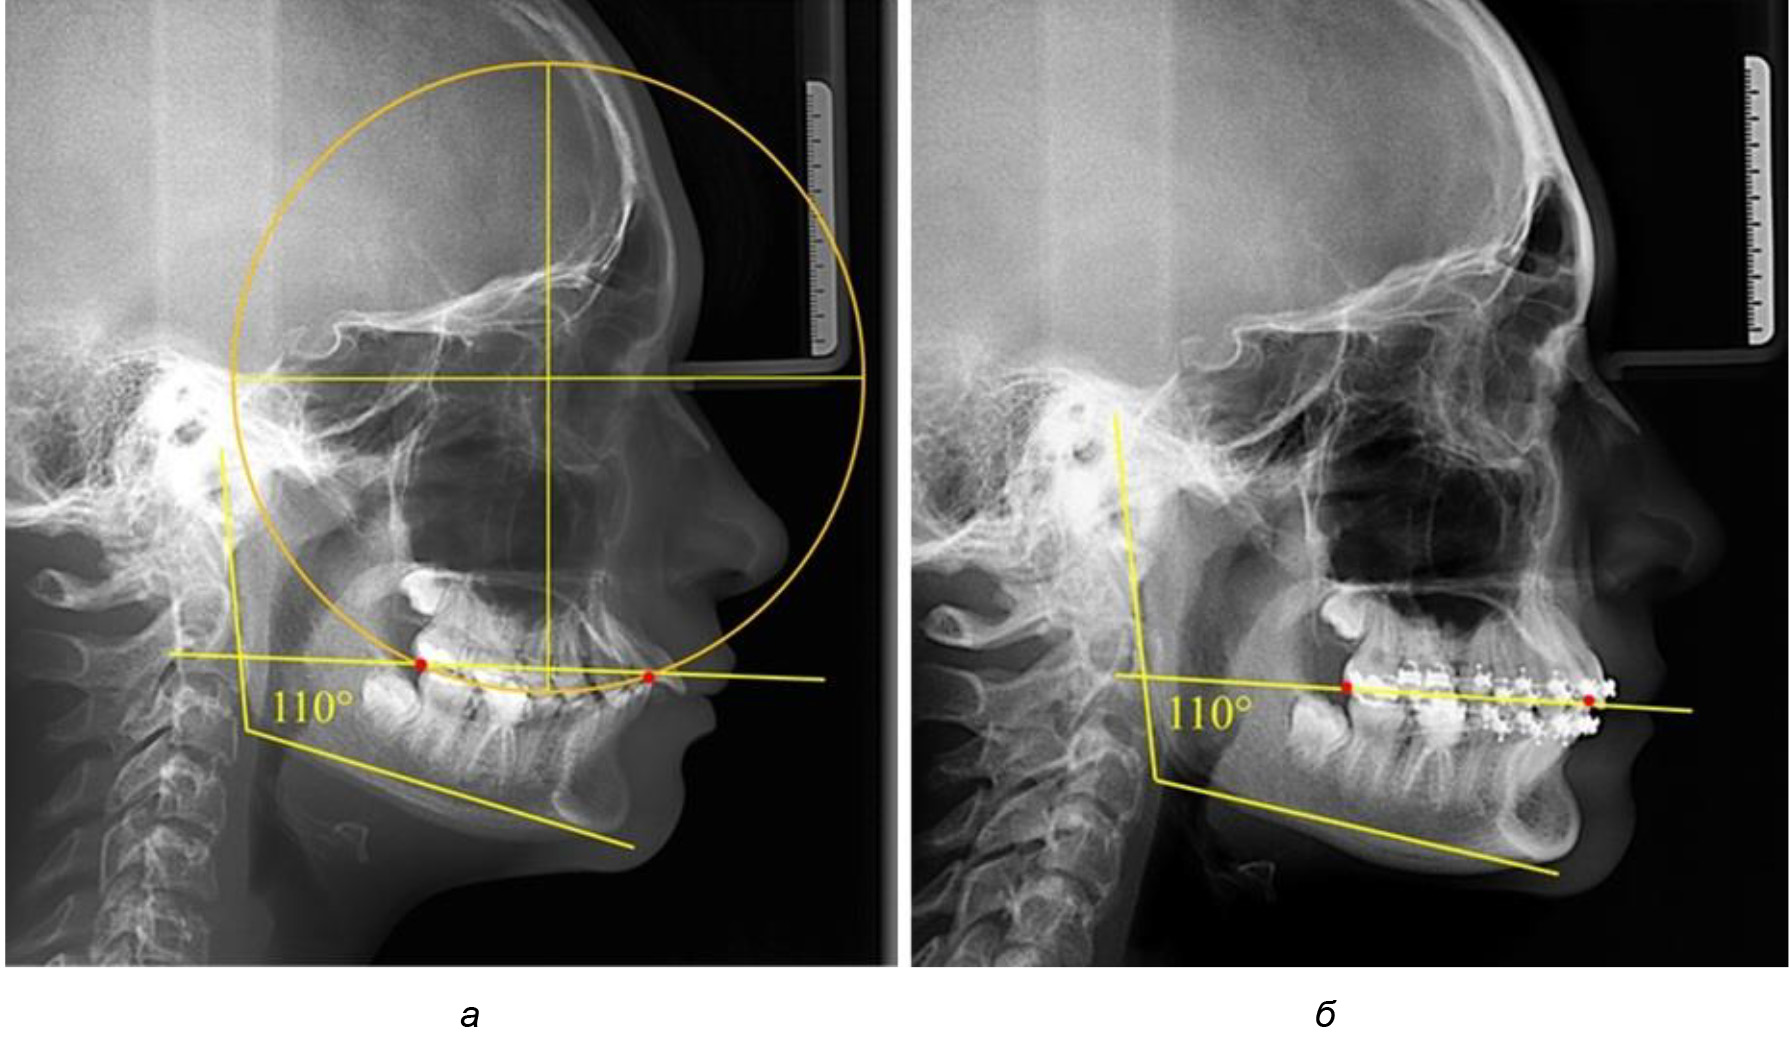

При анализе латеральных ТРГ устанавливали реперный окклюзионные точки в переднем и боковом отделе. Передняя точка устанавливалась на режущем крае нижнего медиального резца, которую в клинике ортодонтии обозначают как vPOcP. Дистальная точка второго нижнего моляра обозначалась как hPOcP. Измеряли расстояние между окклюзионными точками, что определяло сагиттальный размер окклюзионной линии. Использование программ PowerPoint позволило проводить окружность, проходящую по линии смыкания зубов через окклюзионные точки. Измеряли радиус окружности. Учитывая вариабельность размеров окклюзионной линии и радиуса окружности, определяли относительный показатель через отношение радиуса круга к длине сагиттального размера окклюзионной линии. Глубину окклюзионной кривой измеряли от точки наибольшей выпуклости до окклюзионной линии (рис. 1). На ортопантомограмме (ОПТГ) также соединяли окклюзионные точки правой и левой стороны и измеряли глубину окклюзионной кривой от точки наибольшей выпуклости до окклюзионной прямой линии. Результаты глубины кривой Spee сравнивали по данным ТРГ и ОПТГ.

Рис. 1. Метод определения кривой Spee на ТРГ (а) и на ОПТГ (б)

Деление величины радиуса круга к длине окклюзионной линии составило 1,623 ± 0,02. Таким образом, для определения радиуса окружности, соответствующей кривизне окклюзионного контура боковой ТРГ, необходимо измерить расстояние между передней и задней окклюзионными точками и последующим умножением полученной величины на число Фибоначчи (рис. 2).